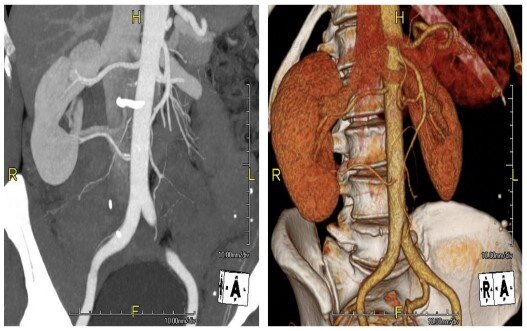

新型影像学和计算机辅助三维重建下的解剖结构细化:可以更好的减少缺血时间,尽早开放阻断的血管,间歇性阻断血管,超选阻断和无阻断血管。

新型节段性肾脏解剖: 精准描述肿瘤分割部位,大小和血供;计算机辅助PVA模型: 依据术前影像计算剩余实质体积,评估术后发生慢性肾功能不全的概率